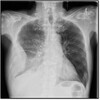

Perfectly

14

Q

What is another name for IRDS?

A